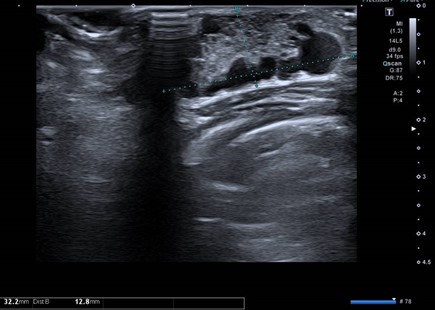

Para realizar el diagnóstico diferencial entre estas entidades clínicas, la ecografía resulta de gran utilidad. El tejido mamario en la intumescencia mamaria neonatal es relativamente hipoecoico, mientras que el aumento en la ecogenicidad es característica de la mastitis. El absceso por su parte será anecoico o ecoico dependiendo de la naturaleza de su contenido. Estos dos últimos presentarán un aumento del flujo en el tejido graso periférico en el Doppler color, pero el flujo en el absceso estará ausente a diferencia de la mastitis debido a la hipervascularización interna4,5 (Figs. 3, 4 y 5).

| Figura 3. Ecografía: glándula mamaria derecha aumentada de tamaño (32,2 mm en su eje longitudinal y 13 mm en su eje anteroposterior) con mínima hiperecogenicidad central y múltiples lesiones quísticas periféricas, sin asociar alteración de la grasa subcutánea |